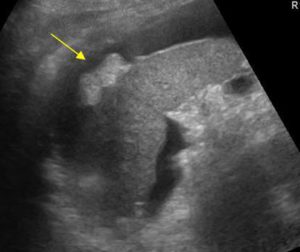

Исследование брюшной полости и забрюшинного пространства (ЗБП) позволяет провести тщательный осмотр не только органов ЖКТ (желудочно-кишечного тракта) и мочевыделительной системы, но и находящихся здесь кровеносных сосудов. В ходе процедуры отчетливо визуализируются паренхиматозные (плотные) ОБП, при использовании допплерографии удается изучить кровообращение в крупных сосудах и более мелких, питающих сами органы.

Пациент лежит на кушетке, на спине. Врач-узист наносит специальный гипоаллергенный гель на кожу живота пациента (для улучшения контакта) и датчик прибора, затем начинает осмотр. В некоторых областях живота датчик под нажимом руки врача как бы углубляется внутрь, обеспечивая максимально близкое расстояние с органом.

Иногда, для улучшения видимости исследуемого участка, например, печени и селезенки, скрытых под реберной дугой, необходимо будет сделать глубокий вдох и задержать дыхание. В этот момент органы немного смещаются книзу, что способствует их лучшей визуализации.

Ультразвуковые волны легко проходят через кожные покровы, отталкиваются от изучаемого органа и отображают результат на мониторе черно-белой картинкой. Для лучшего контакта с датчиком на кожу пациента наносится специальное гелеобразное вещество.